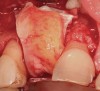

A 53-year-old woman presented with a failing implant in the No. 7 site (Figure 12 and Figure 13). Her desire was to eliminate infection and preserve esthetics. A team effort between the periodontist and restorative dentist to advocate for additional restorative dentistry as well as manage the patient’s expectation of time required was essential. In addition, the patient needed to have realistic expectations of a compromised outcome. Both the restorative dentist and the periodontist informed the patient about the difficulty of achieving this with acceptable esthetic results. Mutual emotional and technical support was required to successfully complete this case, from initial grafting of the defect to placement of anterior restorations (Figure 14 through Figure 23).